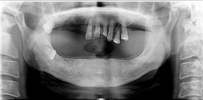

レントゲン写真

治療前 レントゲン写真

治療後 レントゲン写真

60才代 男性

総額:530万円(税別)

治療期間:2年

リスク副作用:経年的変化による補綴物の消耗。ブラッシング不足ですとインプラント周囲炎になります。